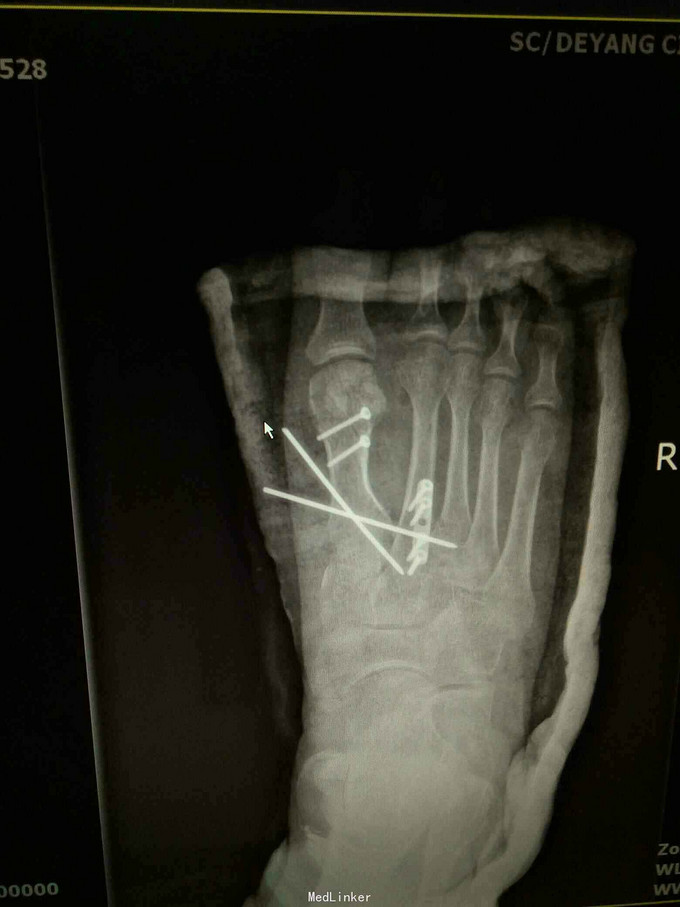

查体:右足畸形肿胀,足背少许擦挫伤,无开放性伤口,明显压痛,右足远远端感觉及血运可。 x片:右足第1、2跖骨基底部骨折,第3跖骨基底部可疑骨折; ct:右足第1~4跖骨骨折。

诊断:右足第1、2跖骨粉碎性骨折;右足lisfrance损伤; 治疗:石膏固定,消肿止痛,行右足跖骨骨折切开复位内固定,第1跖骨钢钉及克氏针固定,第2跖骨钢板固定。